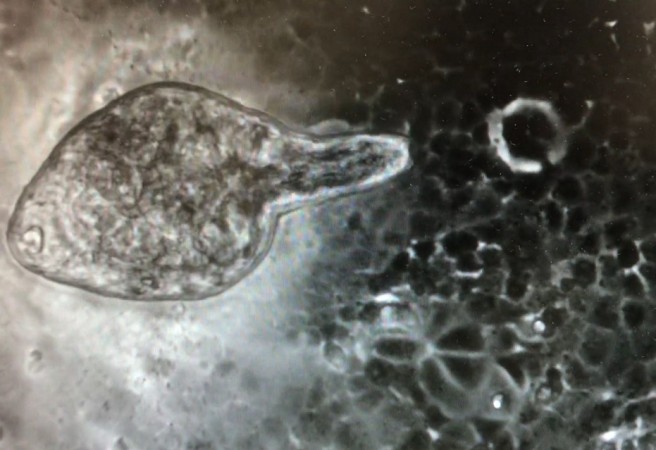

En este estudio, en el que también participa el Instituto de Biología Integrativa de Sistemas (I2SysBio, centro mixto Csic-Universidad de Valencia) se utiliza la especie Fasciola hepatica, helminto parásito con un ciclo de vida complejo que puede infectar a humanos, produciendo fasciolosis, causada por la ingestión de metacercarias (su forma larvaria) en agua o plantas acuáticas. Las larvas ingeridas exquistan en el duodeno y liberan FhNEJ, y luego continúan su desarrollo hasta llegar a la edad adulta en los conductos biliares, pudiendo causar daños en los tejidos.